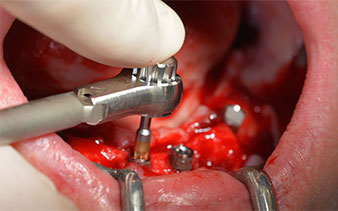

A continuación, se identificó el agujero mentoniano (foramen mentale) como la estructura anatómica límite y se alisó el cortical de la cresta ósea con la pieza de mano recta y una fresa redonda grande (fig. 4).

Es en este momento, donde se hacen patentes las primeras ventajas de Implantmed. El protocolo quirúrgico ya está predefinido y guardado en distintas posiciones fijas que pueden seleccionarse con solo pisar el pedal en la posición «P» o desde la propia pantalla. En este caso, la pantalla iluminada también muestra en grande la velocidad de 35 000/rpm preajustada en la posición 1 (figs. 5 y 6).